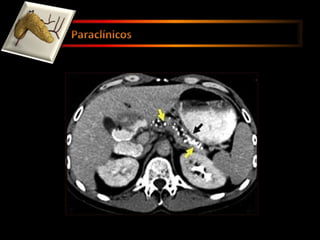

Rayos X de abdomen Exámenes de sangre. ( El hematocrito disminuido -  pancreatitis hemorrágica ) Ecografía  Colangiopancreatografía endoscópica retrógrada  Tomografía computarizada (También llamada escáner CT o CAT.)

Rayos X deabdomen Exámenes de sangre. ( El hematocrito disminuido - pancreatitis hemorrágica ) Ecografía Colangiopancreatografía endoscópica retrógrada Tomografía computarizada (También llamada escáner CT o CAT.)